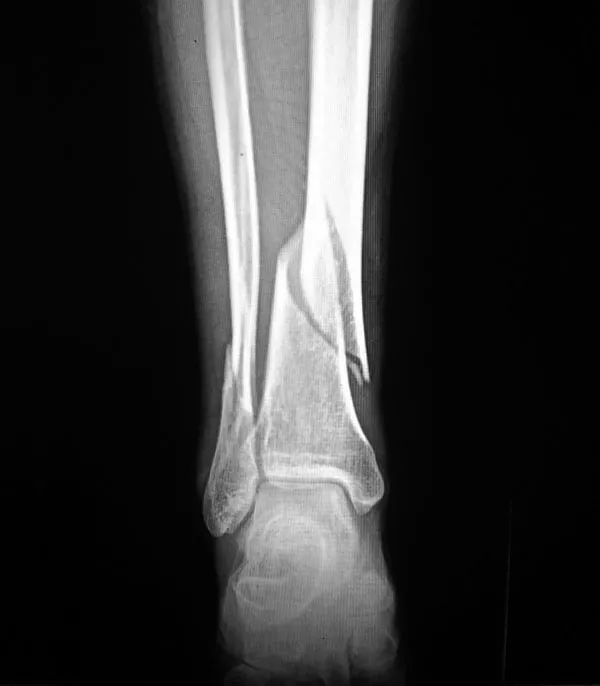

2、骨折:骨質(zhì)疏松癥最常見的并發(fā)癥是骨折,輕微外力即可導(dǎo)致骨折,60歲以上老年人骨質(zhì)疏松并發(fā)骨折者高達(dá)12%。多見咳嗽打噴嚏時、彎腰屈伸撿東西、回頭轉(zhuǎn)身及摔倒等易發(fā)生骨折。骨量丟失20%以上時易發(fā)生骨折,輕者可使活動受限,重者須長期臥床,給社會和家人造成很大負(fù)擔(dān)。老年人骨折可引發(fā)或加重心腦血管并發(fā)癥,導(dǎo)致肺感染和褥瘡等多種并發(fā)癥的發(fā)生,嚴(yán)重危害老年人的身體健康,甚至危及生命,死亡率可達(dá)10%~20%。